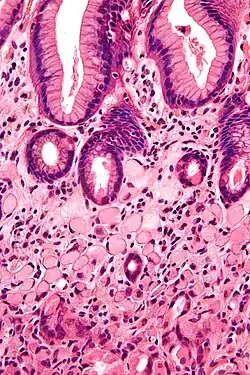

Zegelringcel, zoals te zien bij een colonadenocarcinoom met een vacuole van mucine.